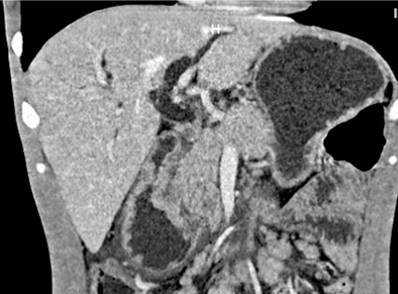

We present the case of a 29-year-old Venezuelan male patient from Santander de Quilichao (Cauca, Colombia) who worked as a deliveryman. For 4 months, he had had pain in the epigastrium, emesis of food and bilious content, soft yellow stools, asthenia, and adynamia. In the last 10 days, he noticed a yellow tinge not associated with acholia or choluria, and in the previous 2 days, a single unquantified fever spike, in addition to the weight loss of 16over the previouslast 4 months. During interrogation, he denied any medical history. In the physical examination on admission, the vital signs were within normal ranges, the sclerae were icteric, the abdomen was painful on palpation of the epigastrium without signs of peritoneal irritation, and there was non-painful mobile bilateral inguinal lymphadenopathy. Blood tests showed serum polymerase chain reaction (PCR): 238 mg/dL, total bilirubin: 8.5 mg/dL, direct bilirubin: 4.9 mg/dL, alkaline phosphatase: 2013 UI/L, amylase: 64 U/L, alanine aminotransferase (ALT): 324 IU/L, aspartate aminotransferase (AST): 168 IU/L and blood count with leukocytes: 10,700/μL, hemoglobin: 12.3 g/dL, hematocrit: 37.7%, platelets: 467,000/μL and neutrophils: 79.8%. The total abdominal ultrasound showed dilation of the intra- and extrahepatic bile duct with an 11 mm common bile duct, without lesions in the liver parenchyma and multiple peripancreatic lymphadenopathy. Subsequently, a simple and contrast-enhanced abdomen CT scan was ordered, confirming a mass at the periampullary level associvarioush multiple mesenteric and retroperitoneal lymphadenopathy (Figure 1).